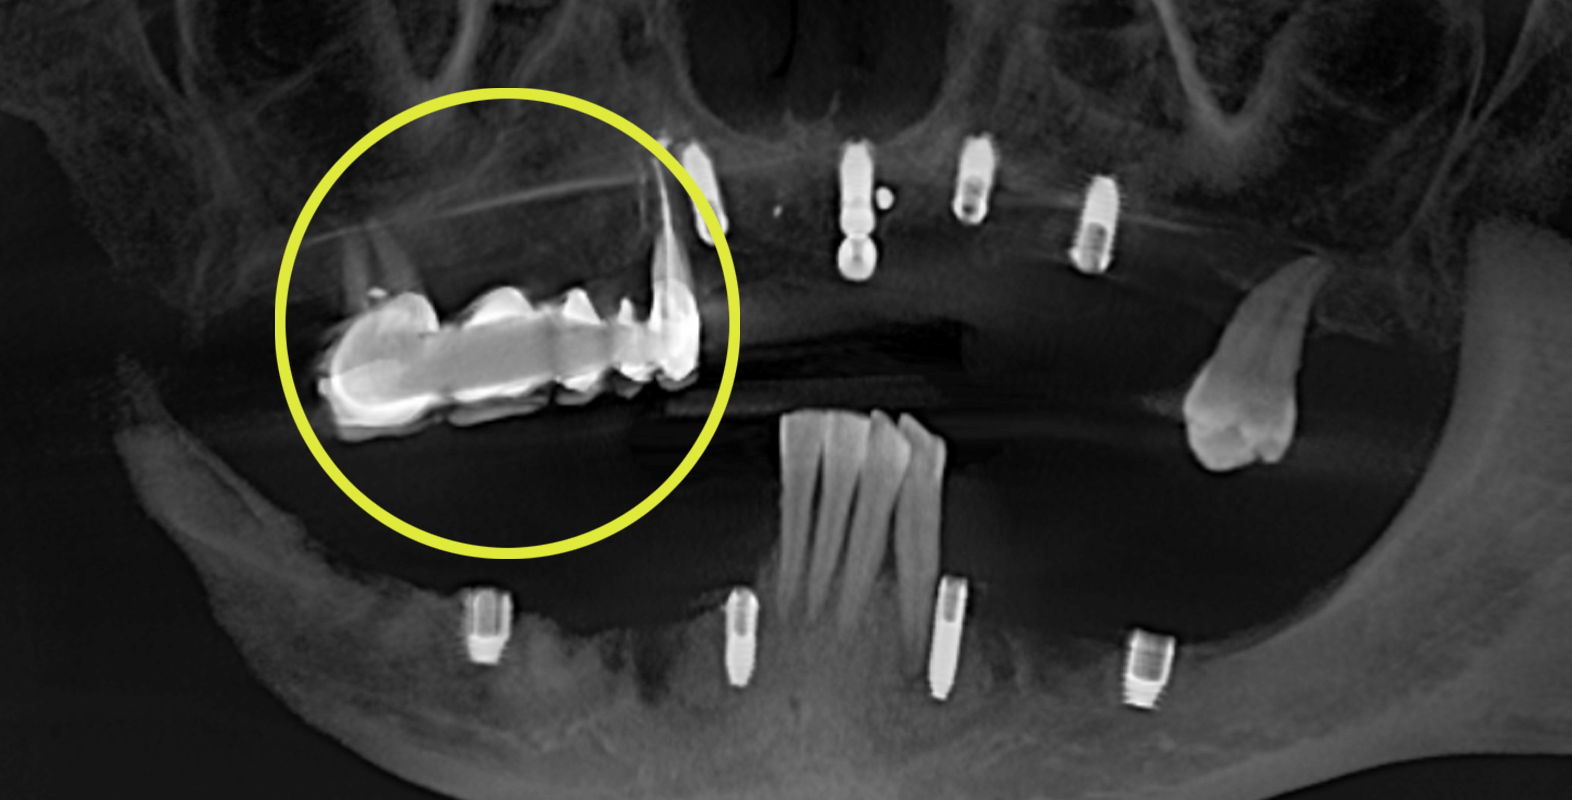

Согласно данным на снимке импланты были расположены не в одной плоскости (нарушена параллельность) и это могло вызвать сложность при протезировании цельнолитой конструкцией, однако при слаженной работе врача и зубного техника был шанс получить положительный результат.

- Опорные зубы мостовидного протеза 1.4 и 1.7 удалить

- В работе применить mock-up модель в два этапа для определения протетической плоскости и параллельности

Протетику для оригинальной имплантологической системы i-System заменили производителем Bicon (США), в связи с довольно длительным (от 4 недель) сроком ожидания, о котором сообщил представитель компании. К тому же, стоимость за эти материалы в результате оказалась ниже.